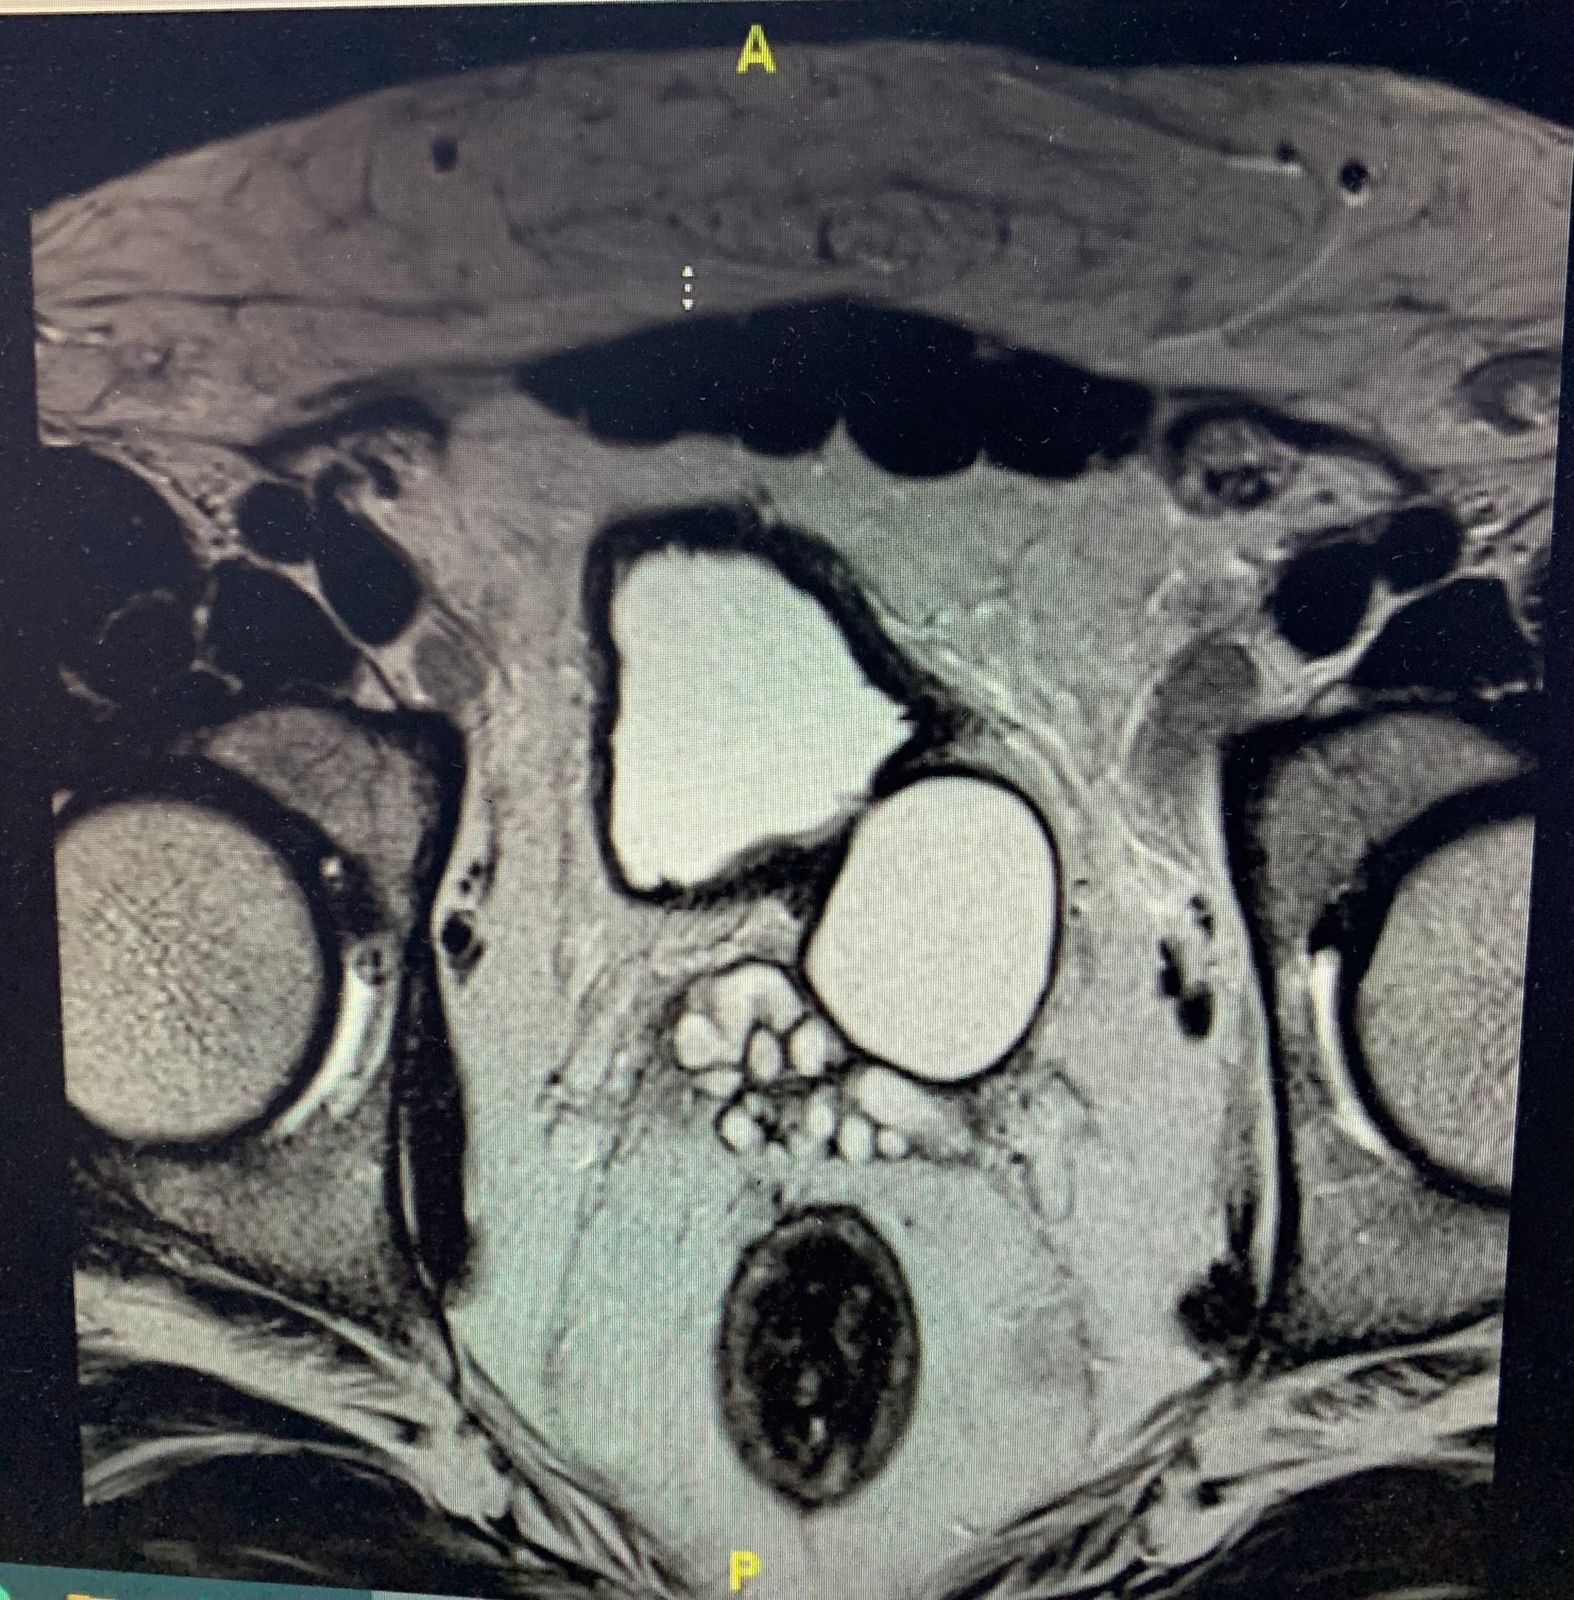

وقال التجمع الصحي في مكة المكرمة ان المريض كان يعاني من آلام مزمنة في الحوض وصعوبة في التبول وبعد الفحص وإجراء أشعة الموجات فوق الصوتية والرنين المغناطيسي قرر الفريق الطبي المعالج إجراء العملية بالمنظار الجراحي وقد تكللت بالنجاح ولله الحمد.

حيث كان المريض يعاني من ” متلازمة زينر الثلاثية ” وهي غياب الكلية على ناحية من الجسم مع تكيس الحويصلة المنوية خلف المثانة البولية وانسداد قناة القذف على نفس الناحية ورغم صعوبة التشخيص في هذه الحالات بسبب ندرتها وأعراضها غير المحددة مثل الآلام الحوض وعسر التبول المستمر .